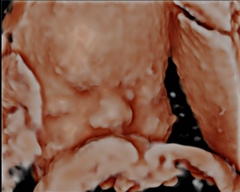

@Kittycaz Honestly I'm a bit let down, got 56 pictures but only 8 of them are actually clear, my child was nose to nose with my placenta so had to keep moving on my side to have a get his face away and have a good look 😂😂 can't be helped but got to see his face so all good.. definitely not worth the £99 that I paid though! X

@Kittycaz hahaha aww I know what you mean! That second picture is gorgeous though 🥰 I can't stop looking at my pictures tbf got 2 clear head shots but a lot of ones where the placenta is in the way.. like this 😂

@MissM94 you have a very beautiful baby such a cute nose. I keep looking at my pictures to becoming a but obsessed.